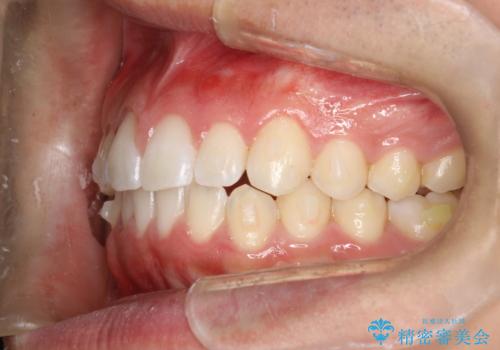

前歯の隙間がきになる インビザラインですきっ歯の治療

- 上の前歯の隙間を主訴に来院されました。

正中に隙間があり、かみ合わせが深い過蓋咬合という状態でした。

インビザラインにて矯正治療を行いました。

しっかり使っていただけたので、スムーズに治療を終了することができました。